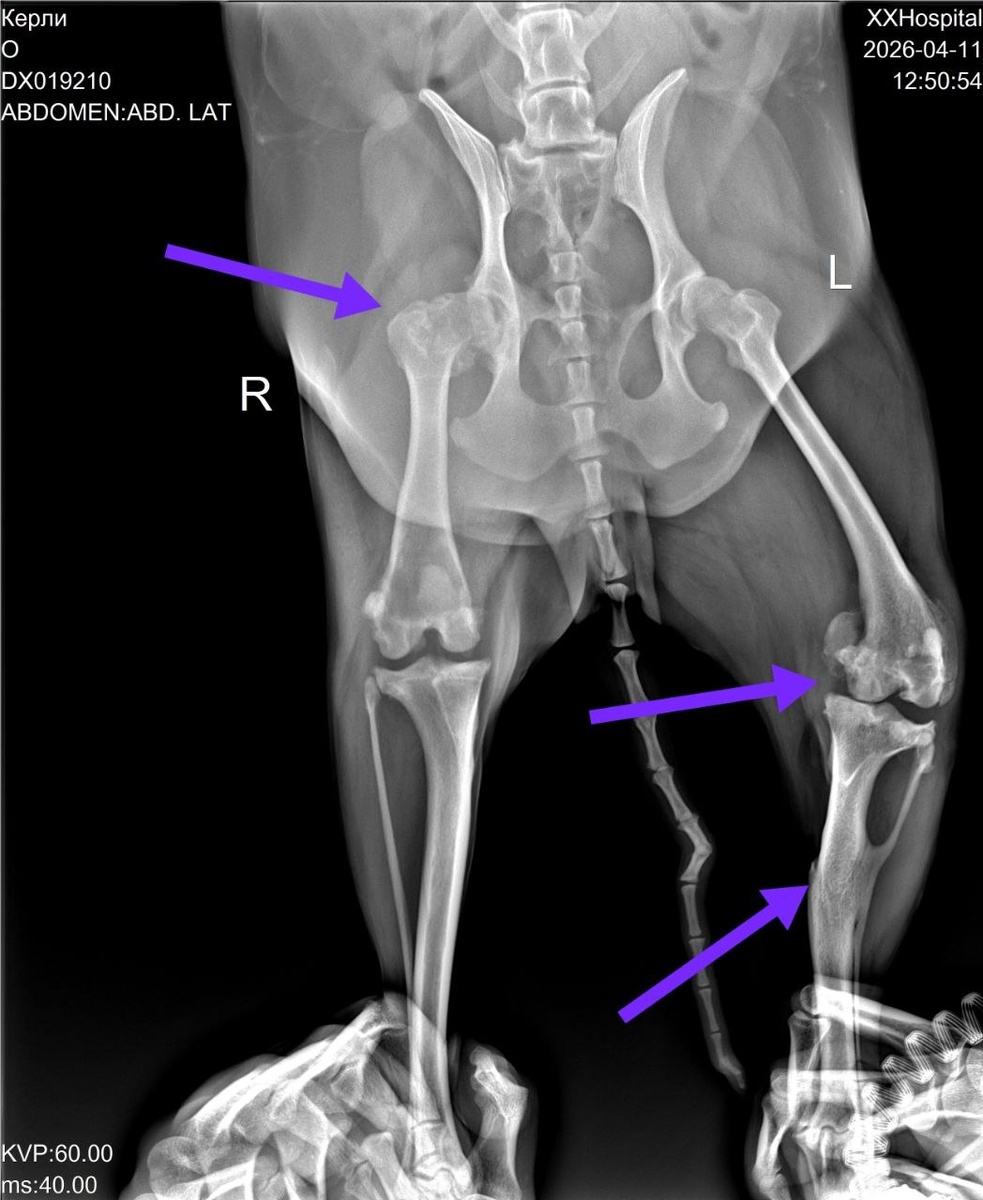

Так вот были мы вместе с Натальей и Керли в ветклинике, в очередной раз судили-рядили по операции. Сделали новые снимки, в разных проекциях.

Итог - проблема с тазобедренным суставом остаётся, но это не главное. Основная проблема в суставе другой лапы. Когда-то на этой лапе был перелом голени, кость перекрутилась и неправильно срослась, сместив при этом сустав. Вот это сейчас и болит. А ещё на этом суставе артроз 4 стадии.

Операция, к сожалению, может не принести никакого эффекта. Будем ещё консультироваться с хирургами и терапевтами.